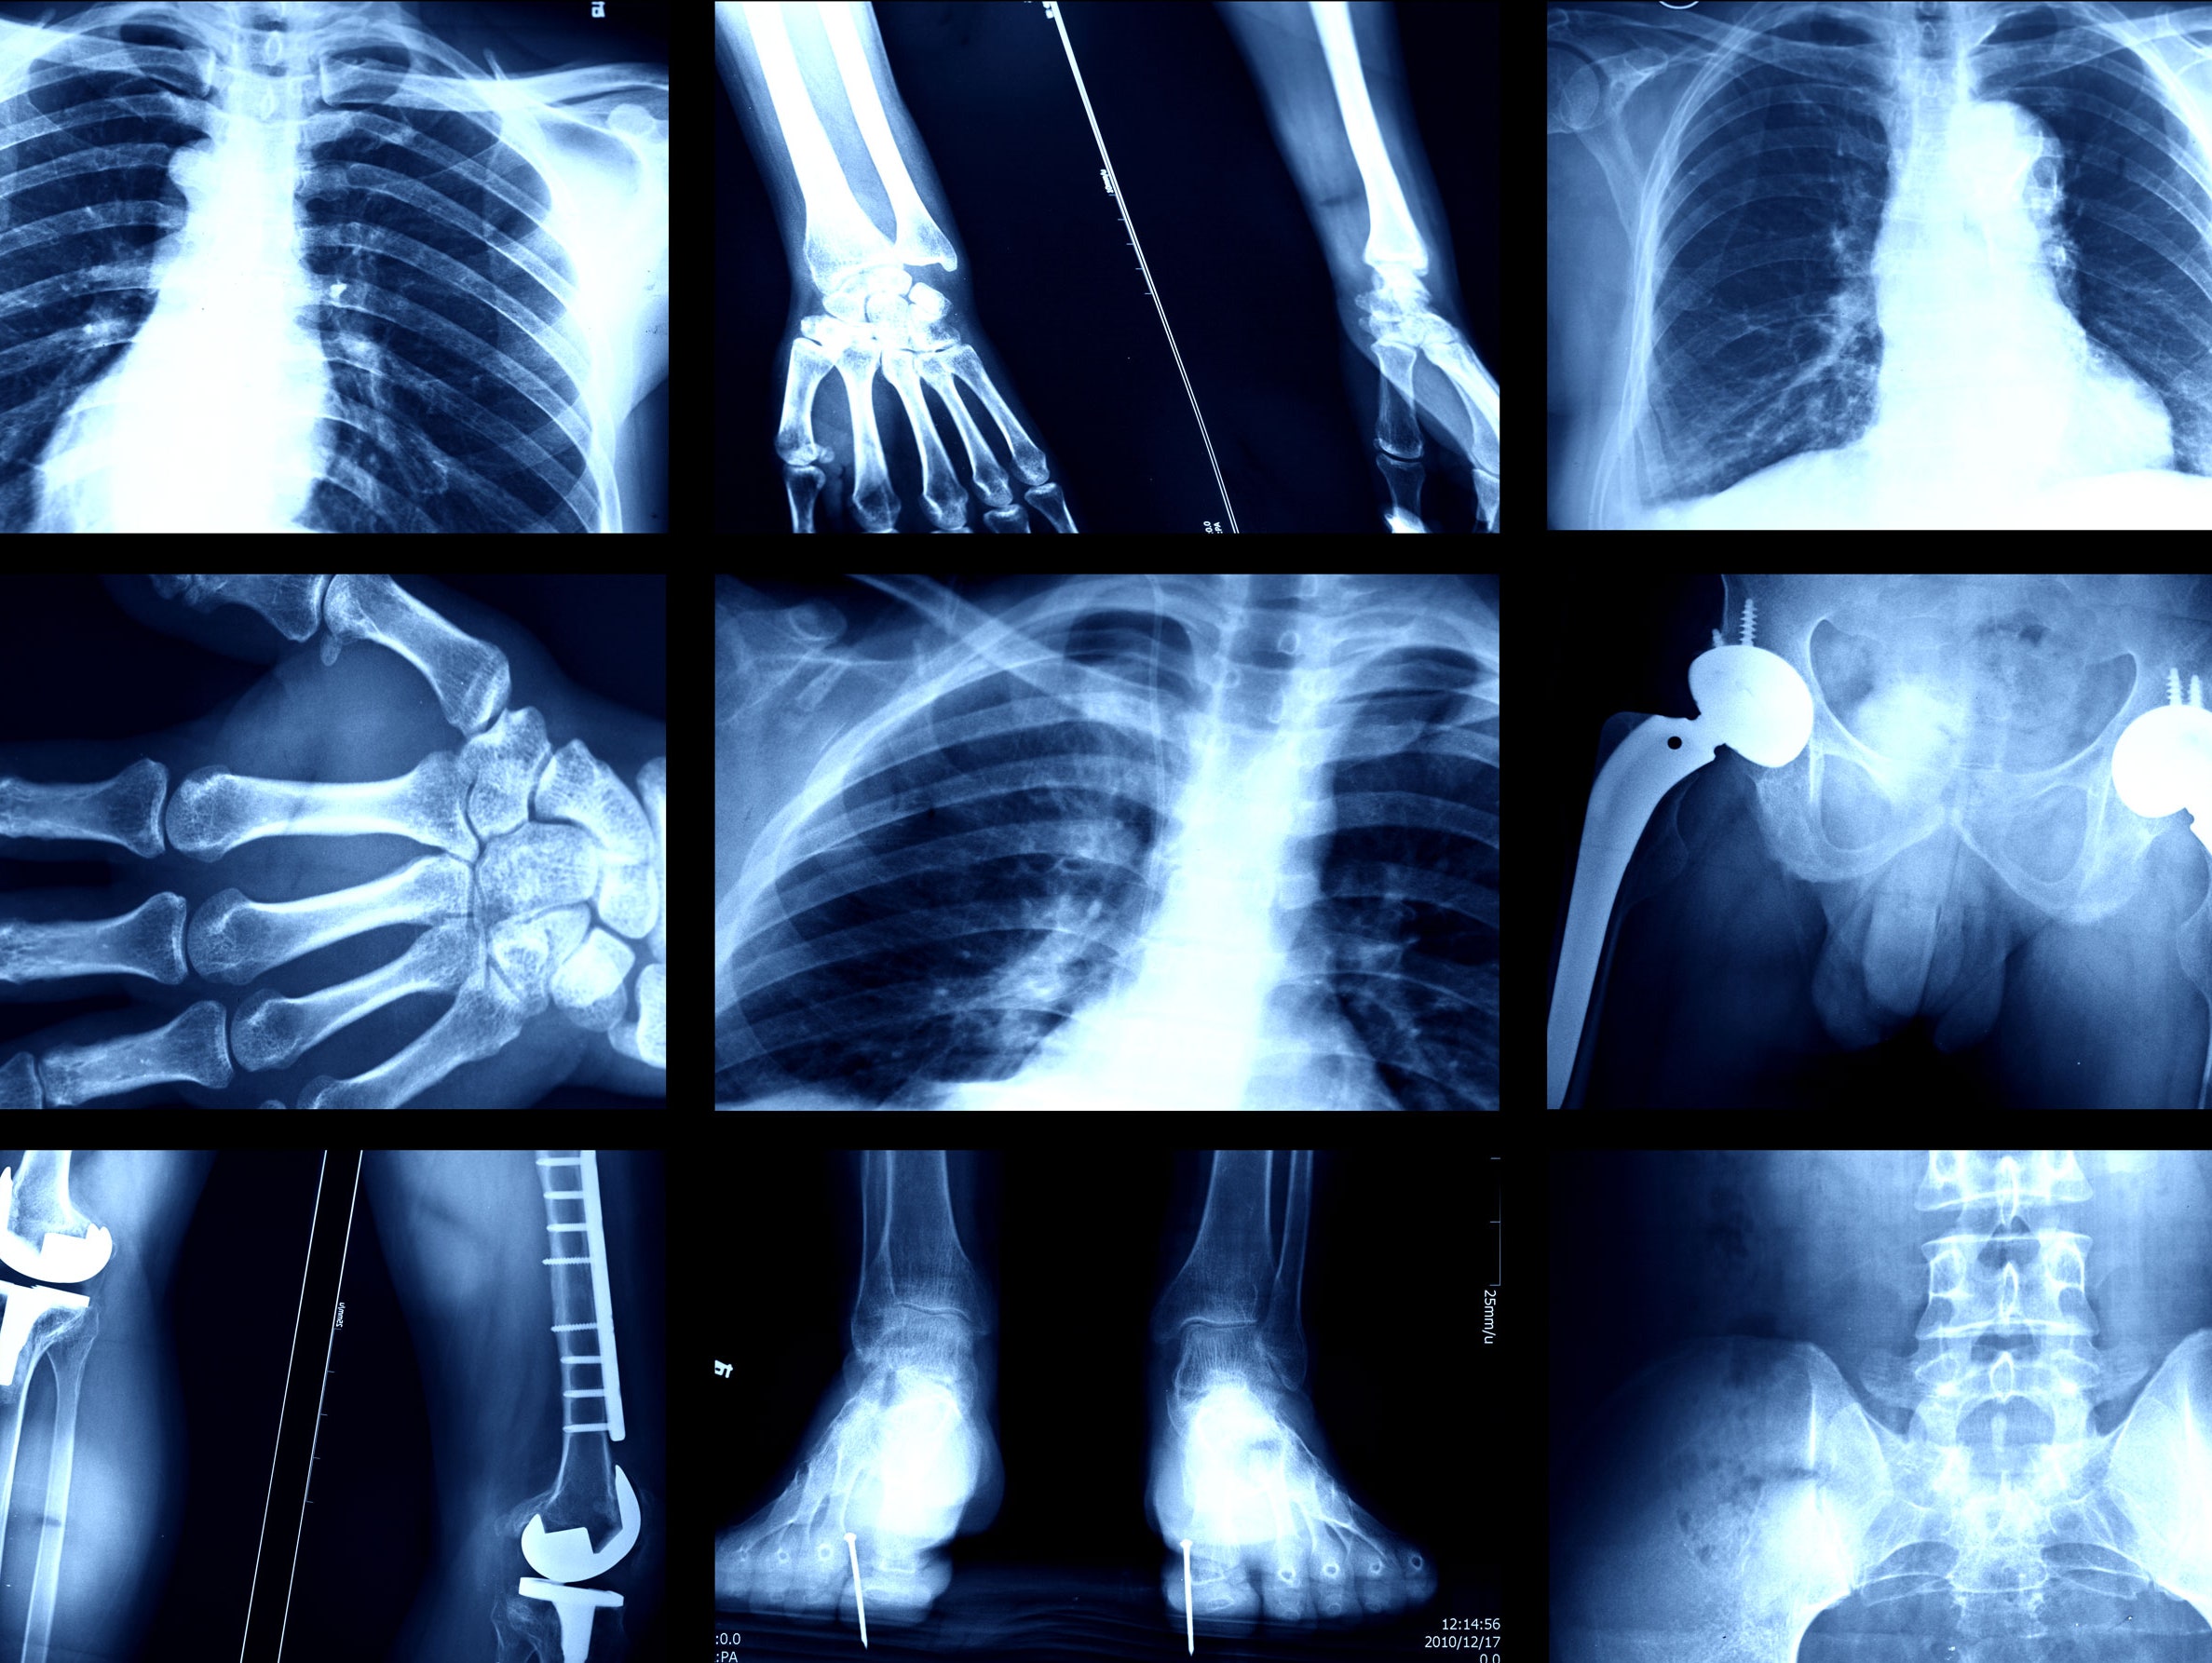

XRAY

A skeletal X-ray is a type of X-ray that specifically looks at your skeleton. Your skeleton is made up of all the bones in your body. An X-ray is a common imaging test that allows doctors to view the inside of your body without having to make an incision. X-rays are waves of electromagnetic radiation that are absorbed differently by different tissues. Bones absorb the electromagnetic radiation well because they are dense. A skeletal X-ray is an incredibly useful tool for your doctor when evaluating your bones. This type of X-ray has revolutionized the diagnosis of skeletal injuries.